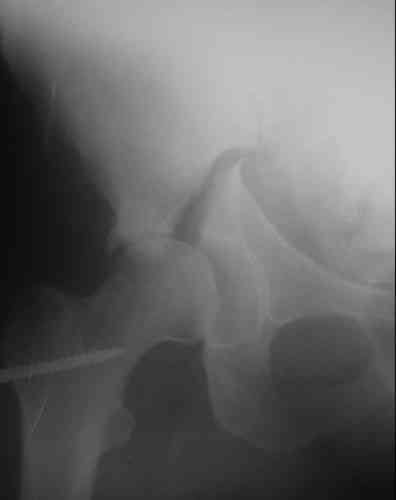

На показанных снимках повреждение правого КПС не очень заметно...

У меня создалось впечатление( одна из РГ), что участок суставной поверхности нагрузочной зоны вертлужной впадины вдавлен( постарайтесь сделать КТ). Если это подтвердиться, то из внутритазового доступа отрепонировать будет невозможно.